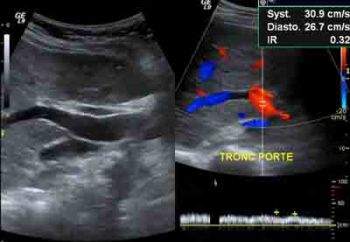

• Le Doppler ?

Le Doppler va se dérouler comme une échographie. Le but de cette technique est essentiellement de vérifier les flux sanguins artériels et/ou veineux, afin par exemple, de montrer un obstacle sur une veine (caillots) qui gène la circulation.